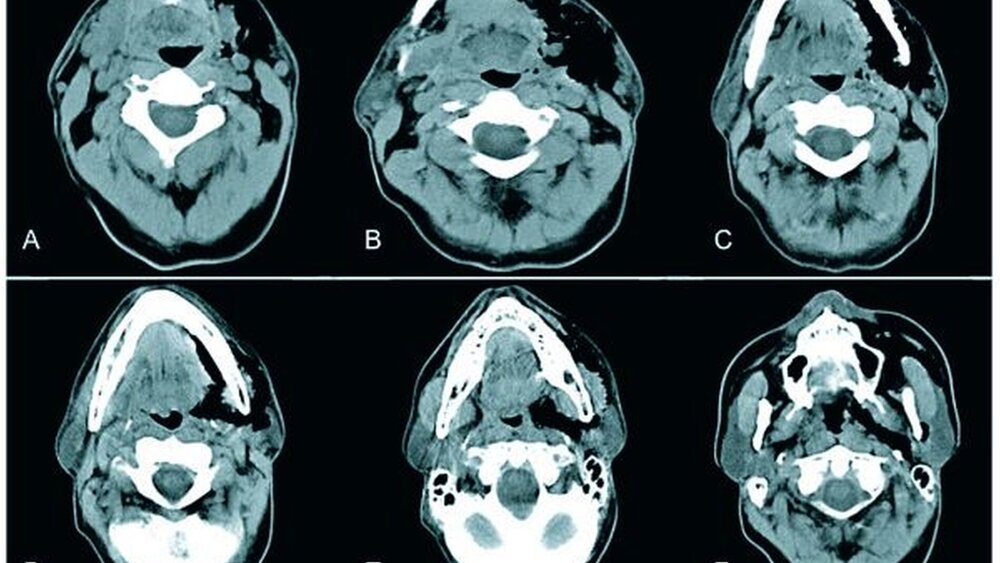

Zur gesicherten Diagnose von Lufteinschlüssen sind neben der klinischen Untersuchung Thoraxröntgenaufnahmen in zwei Ebenen anzufertigen. Die unteren Halsweichteile als auch das Mediastinum sind hier zur Beurteilung ausreichend abgebildet [Terzic et al., 2006]. Zur genaueren Darstellung der Ausdehnung von Emphysemen ist eine Computertomografie des Kopf-Hals-Thorax-Bereiches empfehlenswert [Lopez-Pelaez et al., 2001].

Dentalanamnestisch berichtete der Patient, dass die konservierenden und prothetischen Restaurationen vor etwa fünf Jahren erneuert wurden. Vor über 25 Jahren wurde Zahn 36 endodontisch behandelt und nachfolgend eine Wurzelspitzenresektion mit retrograder Amalgamfüllung durchgeführt. Halbjährlich stellte sich der Patient zur zahnärztlichen Kontrolle vor und ließ regelmäßig sein Gebiss professionell reinigen. In der ersten klinischen Untersuchung zeigte sich eine teigige, leicht erythematöse Schwellung der linken unteren Gesichtshälfte. Die Haut war weich und eindrückbar. Teilweise ließen sich Krepitationen auslösen. Die maximale Mundöffnung war mit 26 mm deutlich gemindert. Intraoral zeigte sich eine dezente Rötung der Gingiva im Bereich der mesiobukkalen Wurzel des Zahnes 36. Die übrigen Schleimhäute inklusive Oropharynx und Tonsillenregion waren reizlos. Bei der Beurteilung des Zahnfleisches fiel an Zahn 36 im Bereich der mesiobukkalen Wurzel eine vestibuläre Rezession von drei Millimetern auf. Die resezierte mesiobukkale Wurzel war bis apikal sondierbar.

Der Patient wurde aufgrund der progredienten Schwellung mit zunehmenden Schluckbeschwerden stationär zur Überwachung und intravenösen kombinierten Breitbandantibiotikagabe mit Cefuroxim einmal zwei Gramm sowie Clindamycin dreimal 600 Milligramm aufgenommen. Unter dieser Therapie nahm das Emphysem ab und die Schluckbeschwerden besserten sich. Nach Abklingen der Symptomatik wurde der Patient zwei Tage später bei unauffälligen Entzündungsparametern nahezu beschwerdefrei in die ambulante Nachbehandlung entlassen. Die Antibiotikagabe wurde noch für drei Tage per os fortgesetzt. Sämtliche Nachkontrollen waren unauffällig. Der Lokalbefund hatte sich deutlich gebessert: Die Schwellung war rückläufig und im Seitenvergleich der perimandibuläre Bereich nahezu identisch. Das Drückgefühl und die Schmerzen waren nicht mehr vorhanden.